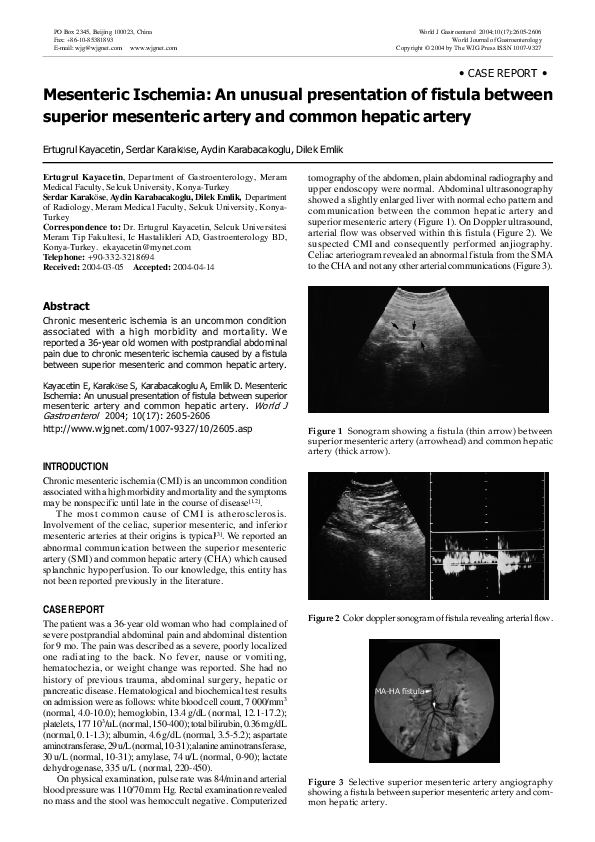

(PDF) Mesenteric ischemia an unusual presentation of fistula between Smoking Related Mesenteric Ischemia acute mesenteric ischemia is the sudden onset of small intestinal hypoperfusion. chronic mesenteric ischemia, also called intestinal angina, refers to episodic or continuous hypoperfusion of. more than 90% of cases of chronic mesenteric ischemia are related to progressive atherosclerotic disease that affects the origins of the. endovascular and hybrid methods are being increasingly used to treat. Smoking Related Mesenteric Ischemia.